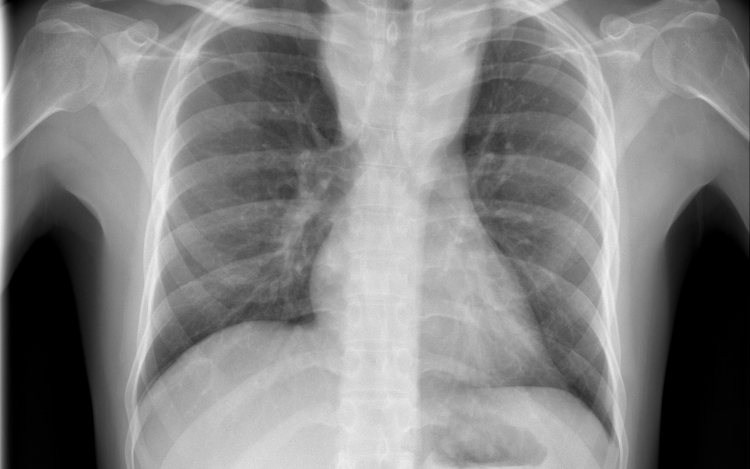

Átlagosan 4,3 százalékkal csökkent az új tuberkulózisos (tbc-s) esetek száma 2010 és 2014 között az Egészségügyi Világszervezet (WHO) 53 országot magába foglaló európai régiójában.

A becslések szerint 2014-ben 340 ezer európai betegedett meg tuberkulózisban, ami százezer emberre vetítve 37 esetnek felel meg. Azzal, hogy 2010 és 2014 között átlagosan 4,3 százalékkal csökkent az új esetek száma, az európai régió teljesítette azt a millenniumi fejlesztési célt, hogy 2015-re visszafordítja a tbc terjedésének tendenciáját.

Magyarországon biztonságos a tbc-re vonatkozó epidemiológiai helyzet: 2014-ben nyolc új eset jutott százezer lakosra, és az előzetes adatok szerint ugyanez igaz a 2015-ös évre is. Így a WHO Magyarországot az alacsonyan átfertőzött országok között tartja nyilván. Alacsony a multirezisztens esetek száma - 2014-ben hét új esetet észleltek -, valamint a gyermekkori megbetegedéseké is: 2014-ben hat 14 éven aluli gyermek betegedett meg.

A WHO a legnagyobb kockázatnak kitett csoportok célzott tbc-szűrését javasolja, Magyarországon 2014 óta eszerint szervezik meg a kötelező tüdőszűrést.